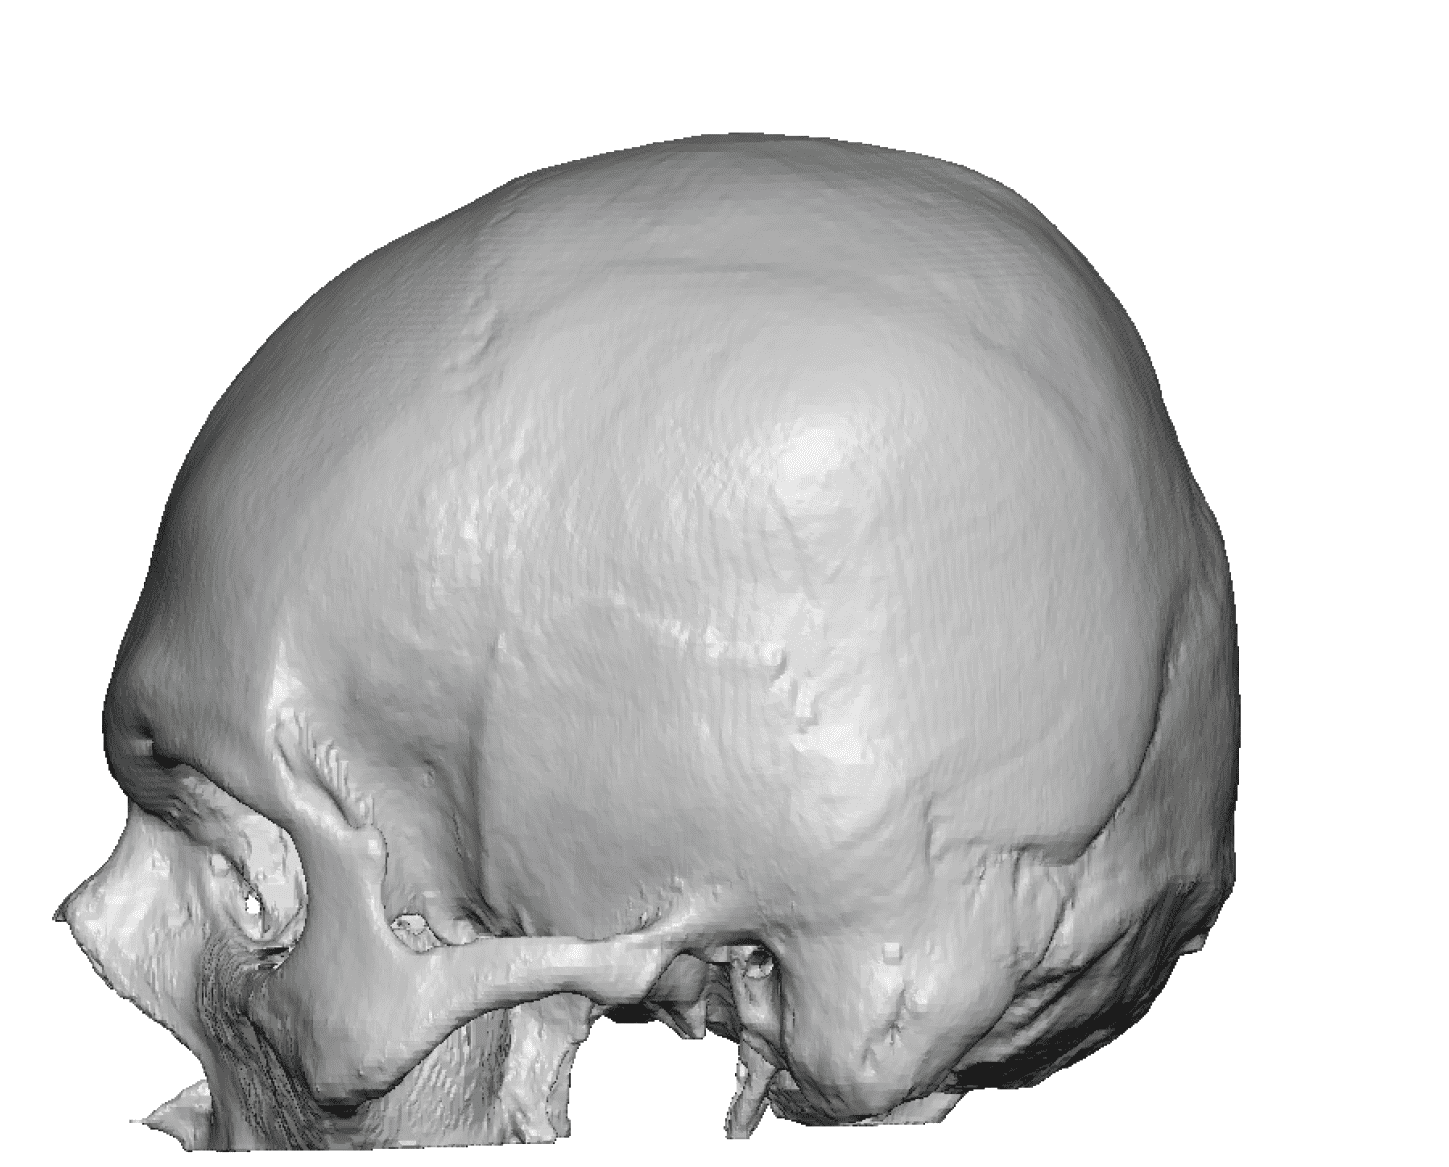

Patient 51

Desire for taller and rounder head shape.

Two stage custom skull implant augmentation technique.

Desire for taller and rounder head shape.

Two stage custom skull implant augmentation technique.